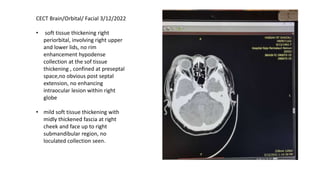

CECT Brain/Orbital/ Facial 3/12/2022

• soft tissue thickening right

periorbital, involving right upper

and lower lids, no rim

enhancement hypodense

collection at the sof tissue

thickening , confined at preseptal

space,no obvious post septal

extension, no enhancing

intraocular lesion within right

globe

• mild soft tissue thickening with

midly thickened fascia at right

cheek and face up to right

submandibular region, no

loculated collection seen.